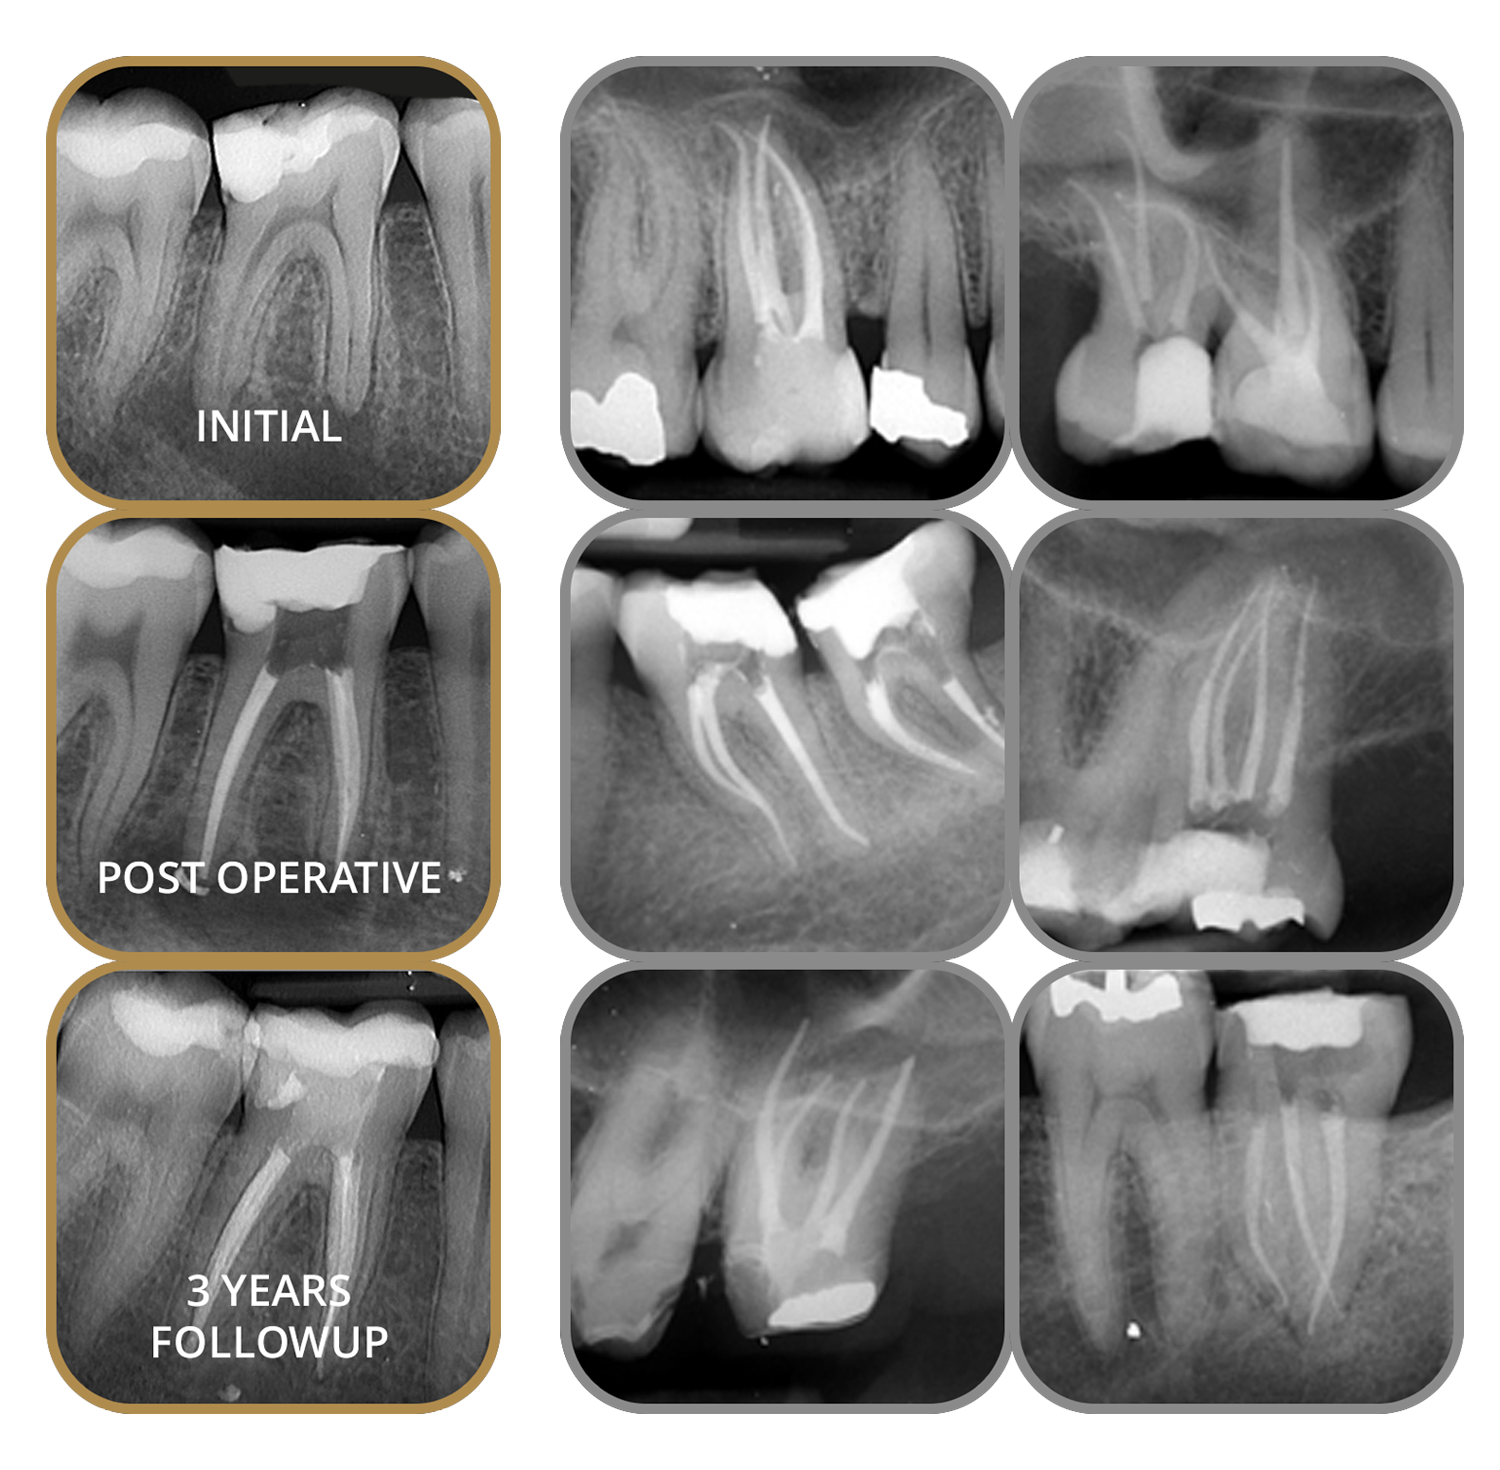

We are pleased to accept referrals for endodontic treatment, providing high-quality care for both simple and complex cases.

Our focus is on delivering predictable outcomes, clear communication and a seamless experience for both referring clinicians and their patients. Whether you are referring for root canal treatment, retreatment or advanced imaging, you can trust your patient will be in safe hands.